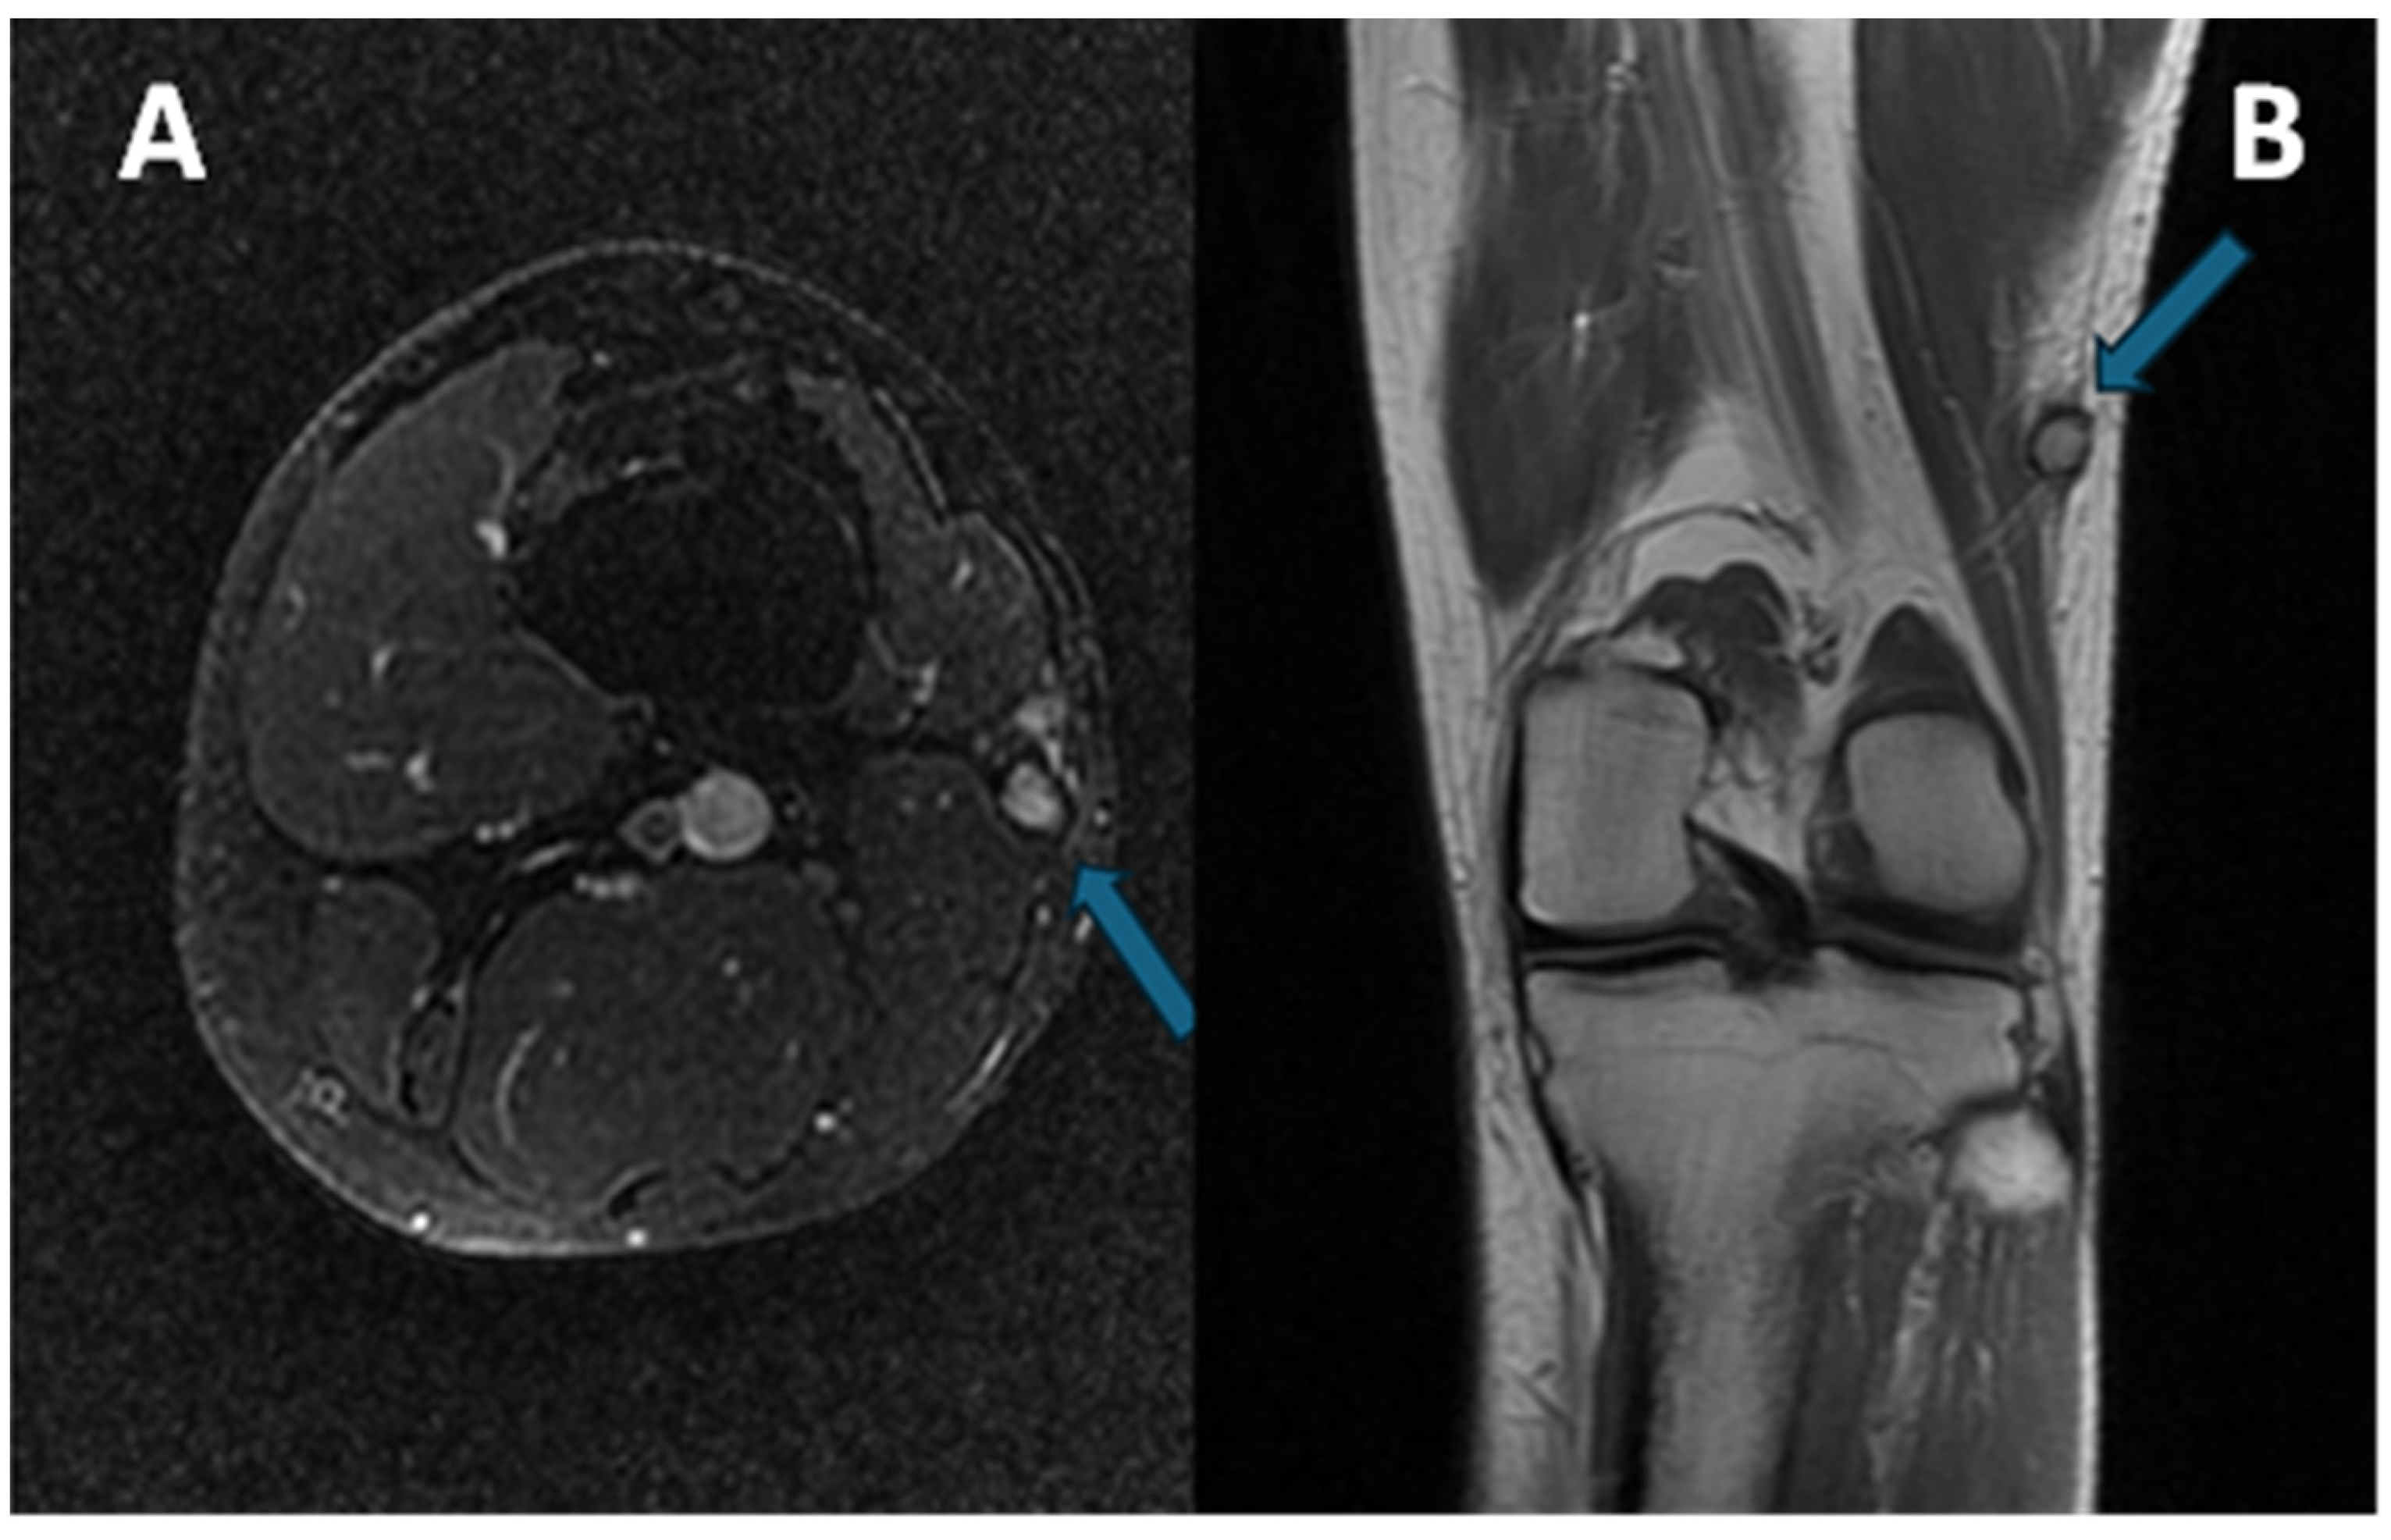

1.1. General Characteristics, History and Epidemiology

1.3. Imaging and Clinical Features

1.3.2. Magnetic Resonance Imaging

3.4. MRI Features

3.4.1. General MRI Features

3.4.2. Peritumoral Edema

3.4.3. Other MRI Features